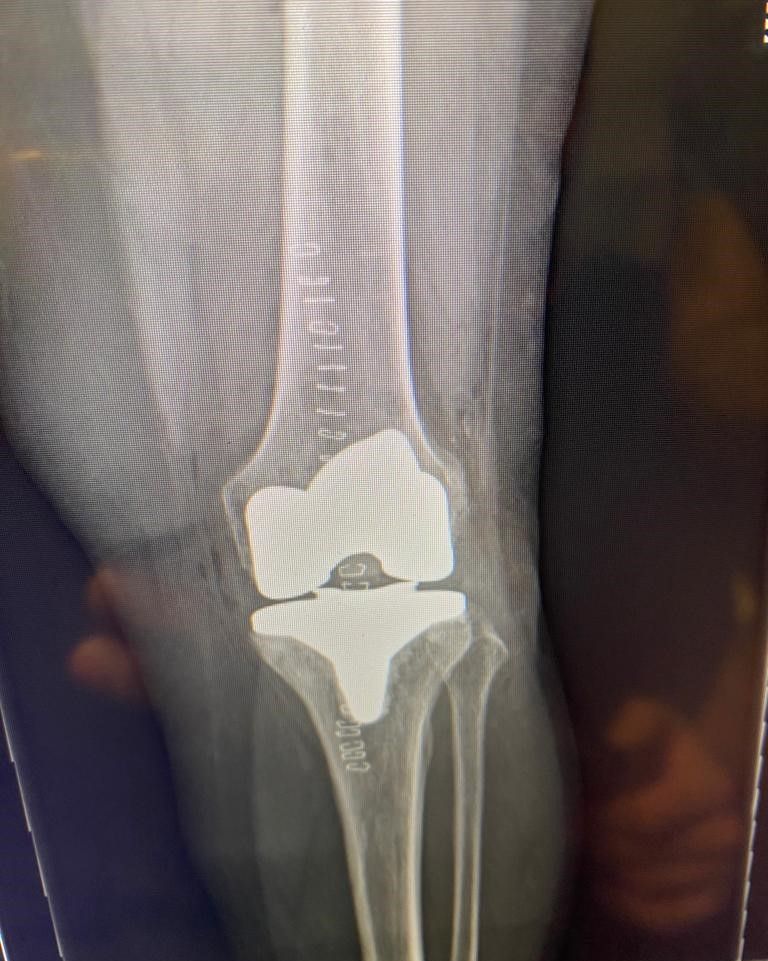

La protesi di ginocchio è costituita da una componente tibiale, una femorale, entrambe in lega di cromo-cobalto, ed un inserto in polietilene che aumenta la congruenza articolare e la stabilità dell’impianto protesico. In genere, le componenti protesiche si fissano all’osso con il cemento, oppure utilizzando degli impianti in tantalio, materiale che si osteointegra completamente entro 3 mesi, senza necessità di cementare.